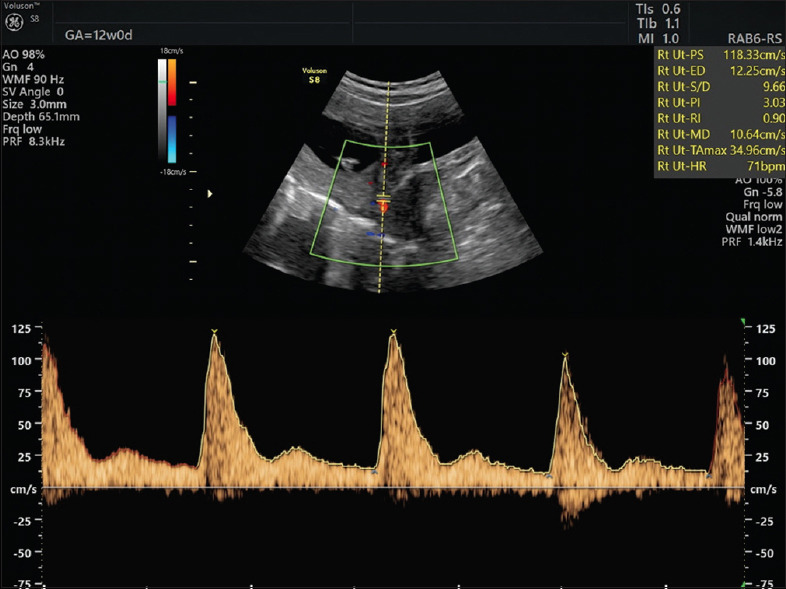

背景:复发性妊娠丢失(RPL)通常源于高凝状态,这加剧了抗磷脂综合征(APS)和血栓形成,导致早期胎盘问题。尽管使用了低分子肝素(LMWH)和低剂量阿司匹林(LDA)等治疗方法,但结果各不相同。本研究建议使用妊娠早期多普勒超声-特别是8周时子宫桡动脉阻力指数(URa-RI)和11-13周时伴有舒张前缺口(Ut-notch)的子宫动脉搏动指数(Ut-PI) -来更好地预测妊娠成功并降低不良后果的风险。目的:本研究的目的是评估URa-RI、Ut-PI和Ut-notch在成功妊娠和不成功妊娠、有不良事件妊娠和无不良事件妊娠之间的差异。环境和设计:该研究在临床环境中进行,采用回顾性队列设计,样本为72例有两次或两次以上RPL发作史的患者。材料和方法:收集8周时URa-RI和11-13周时Ut-PI和Ut-notch的数据。分析中考虑了母亲的特征,包括年龄、体重指数、流产次数、病因和免疫炎症反应。采用统计学分析:对URa-RI、Ut-PI和Ut-notch数据进行比较统计学分析,评估其与妊娠成功和不良结局的关系。对成功和不成功怀孕的变量进行统计比较,并分析不良事件。使用SPSS (IBM,第27版)进行分析。卡方检验用于名义分类和多变量logistic回归校正年龄、体重指数(BMI)、既往妊娠损失、病因和抗核抗体阳性。主要结局(URa-RI、Ut-PI和Ut-notch)以比值比和95%置信区间(ci)进行报告。结果:URa-RI较低(P < 0.0001)。不成功妊娠的URa-RI平均值(0.50±0.09比0.38±0.04,P < 0.0001)也显著高于不成功妊娠。Ut-PI高、Ut-notch阳性导致不良事件风险显著增加,分别为19.4倍、8.1倍(95% CI = 4.2 ~ 51.6、3.12 ~ 20.5,P < 0.0001)。结论:本研究证明了妊娠早期多普勒超声(URa-RI, Ut-PI和Ut-notch)在预测RPL患者妊娠成功和不良事件方面的作用,特别是那些使用低分子肝素和LDA治疗的患者。这些超声标记物可能为管理和预测与血栓形成和APS相关的RPL病例的结果提供有价值的指导。

Background: Recurrent pregnancy loss (RPL) often stems from a hypercoagulable state that exacerbates conditions such as antiphospholipid syndrome (APS) and thrombophilia, leading to early placental issues. Although treatments such as low-molecular-weight heparin (LMWH) and low-dose aspirin (LDA) are used, outcomes vary. This study proposes using first-trimester Doppler ultrasound - specifically, uterine radial artery resistance index (URa-RI) at 8 weeks and uterine artery pulsatility index (Ut-PI) with pre-diastolic notching (Ut-notch) at 11-13 weeks - to better predict successful pregnancies and reduce risks of adverse outcomes.

Materials and methods: Data on URa-RI measured at 8 weeks and Ut-PI and Ut-notch measured at 11-13 weeks were collected. Maternal characteristics - including age, BMI, number of pregnancy losses, etiopathology and immuno-inflammatory response - were considered in the analysis.

Results: Low URa-RI (<0.45) at 8 weeks gives a 16.4 times higher chance for the management to be successful and result in a healthy take-home baby (95% CI = 4.4-61, P < 0.0001). The mean URa-RI was also significantly higher in unsuccessful pregnancy (0.50 ± 0.09 vs. 0.38 ± 0.04, P < 0.0001). High Ut-PI and positive Ut-notch result in a significant increase of adverse event risk, which are 19.4 times and 8.1 times, respectively (95% CI = 4.2-51.6 and 3.12-20.5, P < 0.0001).